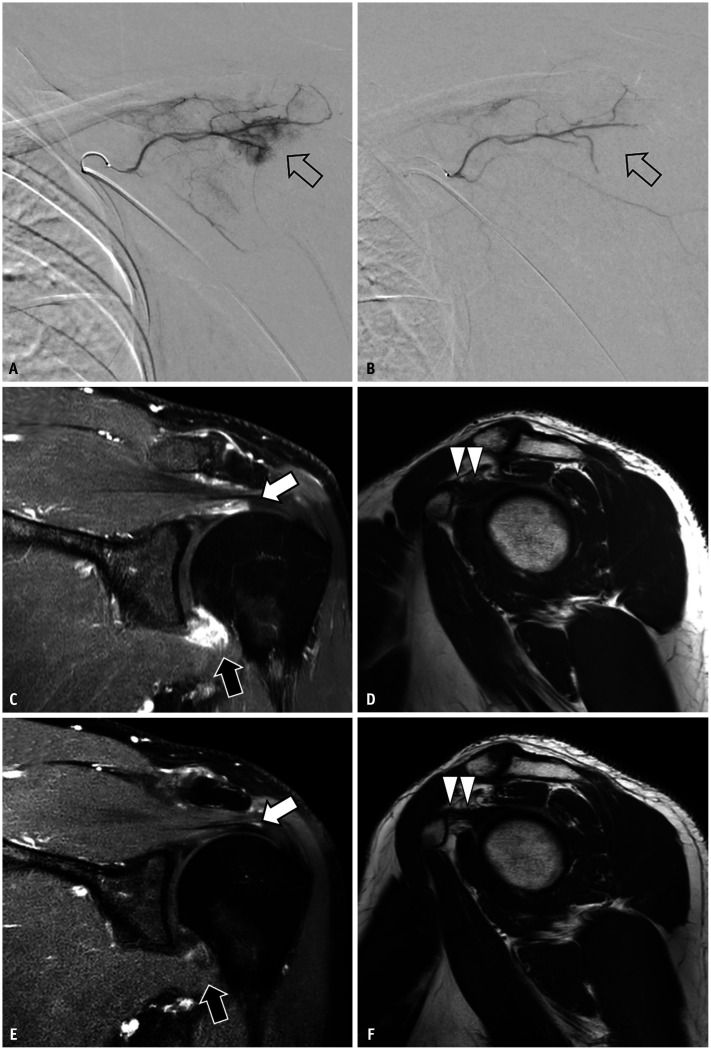

Results: Twenty-five patients (female:male, 14:11; age, 54.9 ± 7.1 years) were included. Significant reductions in average NRS pain scores as well as improvements in Quick DASH scores and range of motion, including anterior flexion and abduction, were observed at 1, 3, and 6 months after TAE (all P < 0.001). MRI analyses revealed that TAE significantly decreased the grades of axillary recess capsule enhancement, rotator interval (RI) capsule T2 signal intensity, and RI capsule enhancement (all P ≤ 0.004).

Conclusion: TAE may be an effective and safe therapeutic approach for AC refractory to conservative treatments, alleviating pain and supporting functional recovery. The observed MRI findings suggest that the effectiveness of TAE for AC may be attributed to the reduction of inflammation and the elimination of angiogenesis.